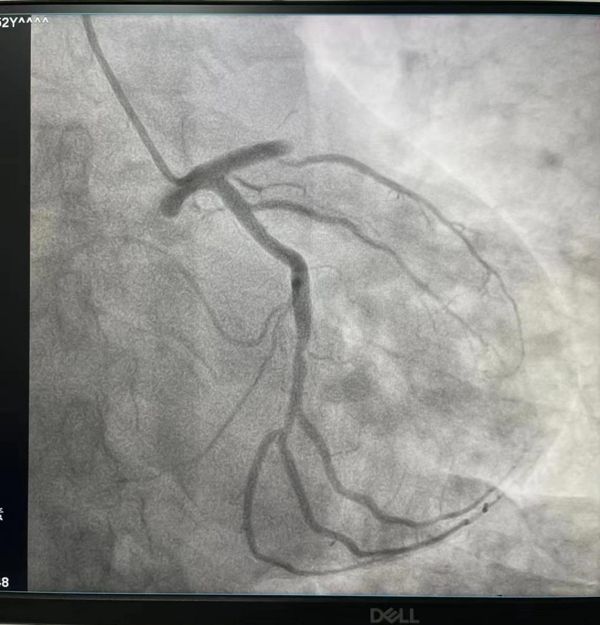

患者病情危重,入院后值班医生赵娟副主任与护士李佳佳、王梅菊紧急将患者送往介入科,开展急诊手术,术中患者持续性胸痛,血压低,赵大夫,睢大夫和郑大夫临危不乱,给予对症处理,造影结果显示:患者前降支完全闭塞,遂进行开通,后置入一枚支架,手术几经波折,险象环生,历经近一个小时,终于完美收官,患者安返病房。此时,患者家属长舒了一口气,对各位医护工作人员表达热烈的感激之情,我科工作人员表示这是我们应该做的,场面异常温馨。